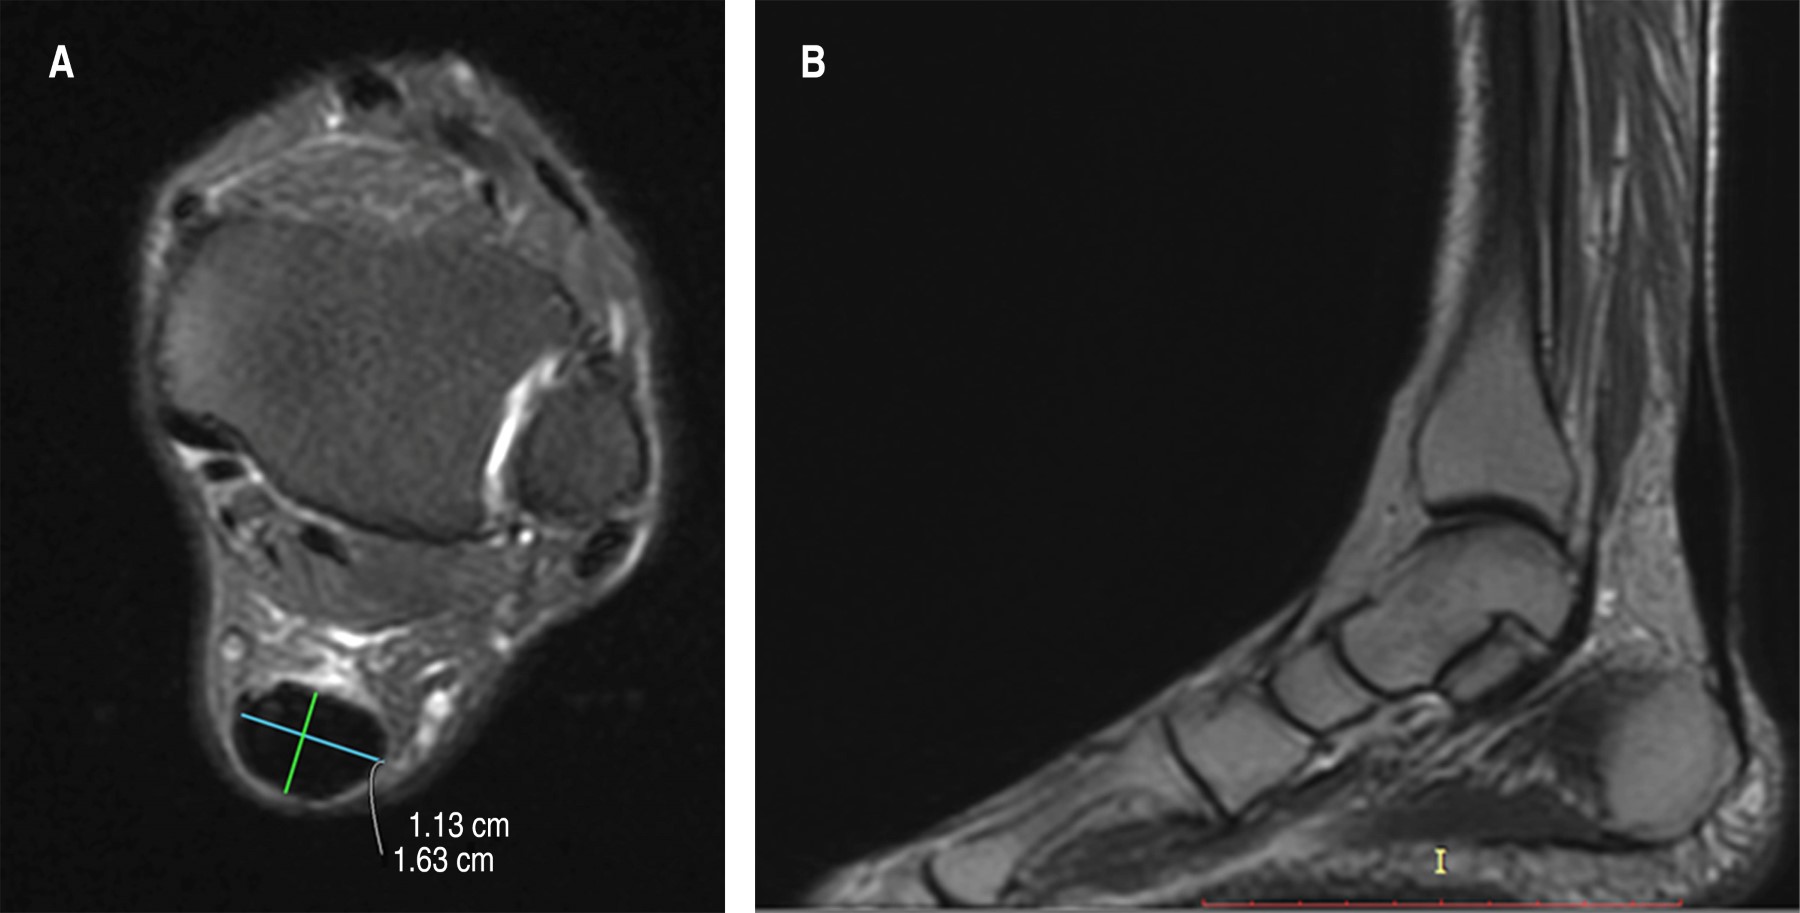

Resonancia magnética simple del tendón de Aquiles en la que se observa aumento de diámetro del tendón de Aquiles e hiperintensidad en grasa de Kager, aumento de volumen en la mayor parte del trayecto del tendón, con aumento de su diámetro e imágenes compatibles con rupturas focales. No hay presencia de nódulos (Figura 4).

Se deben realizar estudios de imagen para complementar el diagnóstico, puede ser un ultrasonido; sin embargo, éste cuenta con la limitante de ser operado dependiente, por lo que en nuestro medio lo que más se utiliza es la resonancia magnética donde se pueden observar las estructuras anatómicas y tejidos blandos y los cambios directos e indirectos en la degeneración del tendón.